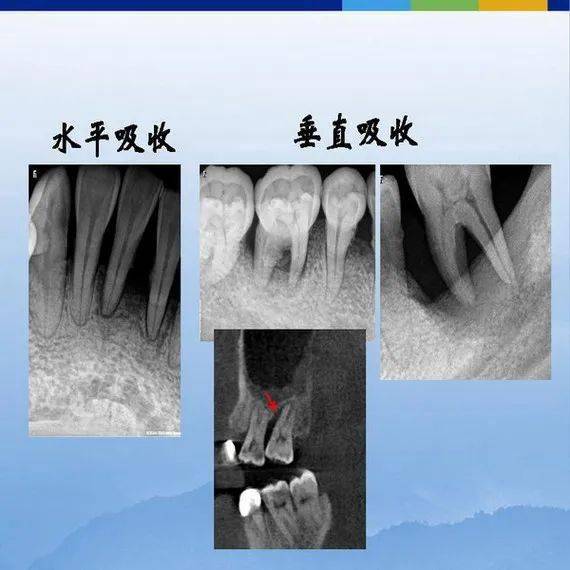

牙各种疾病影像学表现,整理完毕!

牙体牙周正常解剖及常见病x线表现